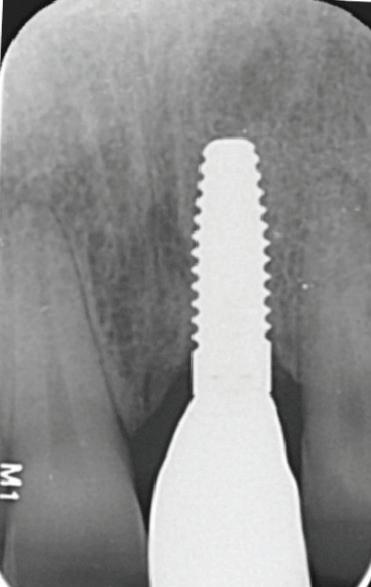

De asemenea, trebuie evaluate anual modificările radiografice. În ședința de inserție a restaurării, se înregistrează o radiografie bitewing standardizată pentru a permite evaluarea anuală a modificărilor osoase din jurul implantului. Remodelarea osului alveolar în primul an este bine documentată și depinde de tipul de implant utilizat; cu toate acestea, nu ar trebui să apară apical de primul filet al implantului. Prin urmare, este importantă abilitatea de a vizualiza filetele implantului pe radiografii. Modificările pierderii osoase de 2 mm sau mai mult după primul an reprezintă un semn de periimplantită. De îndată ce pierderea osoasă este recunoscută, pacientului trebuie să i se recomande terapia imediată pentru a opri procesul de boală.

Utilizarea platform-switch și-a dovedit eficiența în sistemele moderne de implanturi. Însă acum, zona conică inversată oferă mai mult spațiu și un suport mai bun de aderență pentru țesutul dur și moale decât formele cilindrice ale implanturilor, așa cum cum se poate vedea în imaginea următoare.

Suprafața microstructurată din zona conică inversată sprijină atașarea osului și a țesutului conjunctiv. Atunci când marginea acesteia este poziționată subcrestal, este recomandată utilizarea unui material de augmentare (xenogrefă sau os autolog) care poate preveni dezvoltarea țesutului moale în zona conică inversată și poate oferi suport pentru o mai bună osteointegrare.